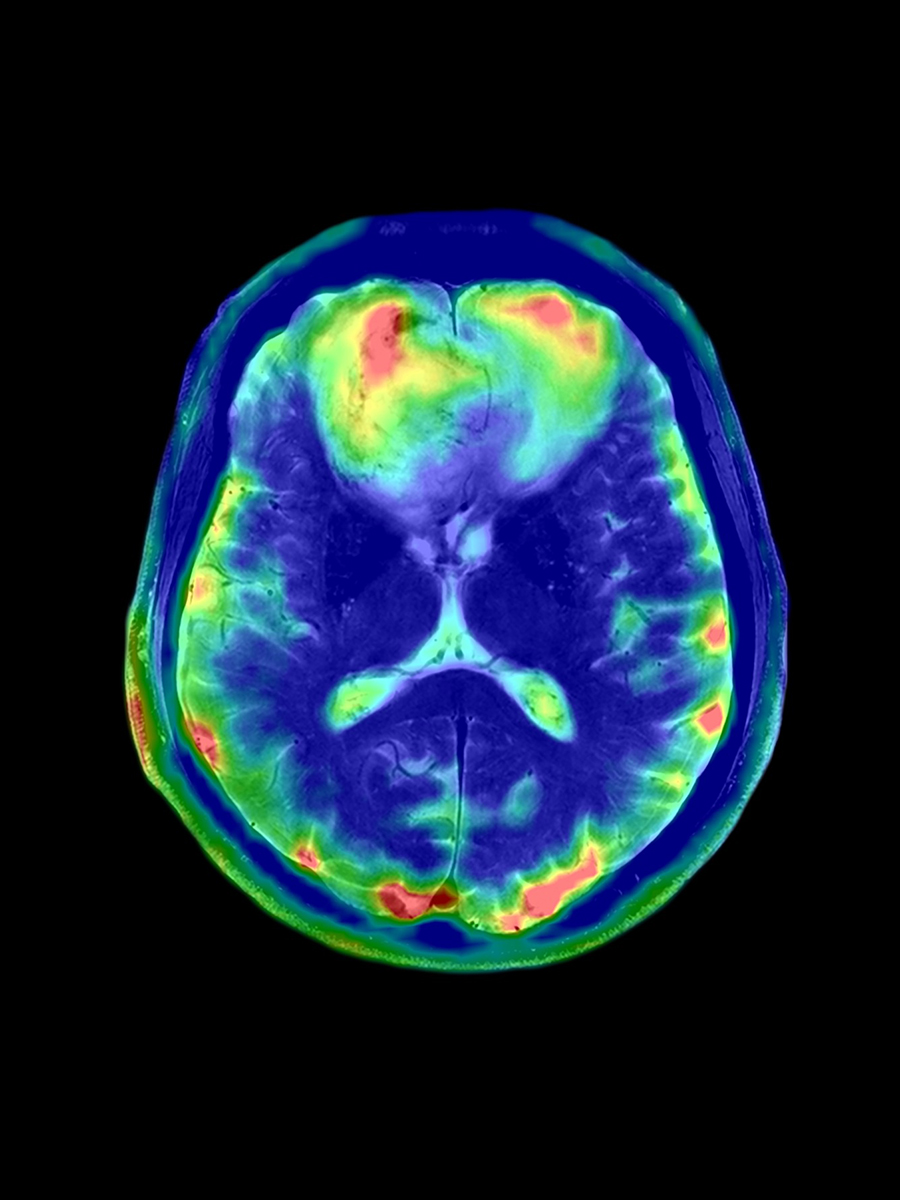

Radiologen und Radio-Onkologen müssen tagtäglich eine immense Anzahl an Bildern auswerten, wofür bei der wachsenden Arbeitslast meist nur wenig Zeit bleibt. Der AI-Rad Companion unterstützt seine Anwender bei der Begutachtung von Bildern und dem Erkennen radiologischer Auffälligkeiten. Mithilfe von Deep-Learning-Algorithmen werden Bilddatensätze automatisch nachbearbeitet, etwa durch das Labeln von Anatomien und dem Vergleichen der Ergebnisse mit Referenzwerten. Auf diese Weise können Nutzer bei Routineabläufen mit ständig wiederkehrenden Aufgaben und hohen Fallzahlen unterstützt werden.

Der AI-Rad Companion steht für eine Produktfamilie, die Lösungen (auch Erweiterungen oder Extensions genannt) für verschiedene Modalitäten und Körperregionen bereitstellt. Um eine konsistente Gestaltung über alle Erweiterungen hinweg zu gewährleisten, wurde UseTree für die Entwicklung der vier Anwendungen Brain MR, Prostate MR, Chest X-ray und Organs RT ins Boot geholt.